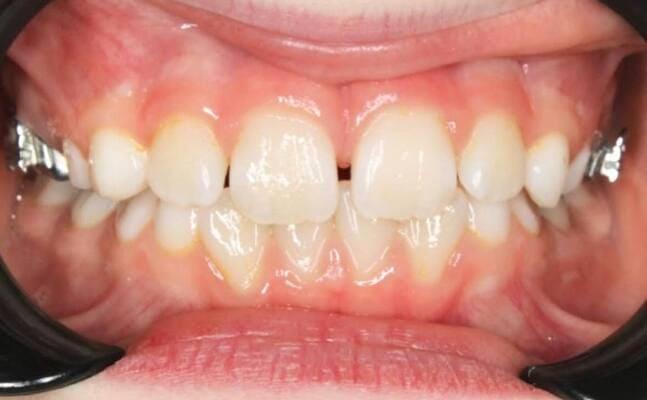

Пацієнт 2 років, уражено десять зубів, шість із яких потребують покриття коронками. В зв’язку зі значним об’ємом та складністю лікування прийнято рішення про лікування в умовах анестезіологічного забезпечення. Раніше була спроба пролікувати ці зуби застарілими методами, які не тільки не є ефективними відносно лікування, а ще і додають дитині комплексів через характерне фарбування зубів. Через високи естетичні вимоги дитини і батьків було прийнято рішення покривати естетичними цирконієвими коронками, як передні так і бічні зуби. Через 2,5 години дитина без інфекції в порожнині рота, з відновленим здоров’ям та естетикою посмішки може кусати, жувати, посміхатись без болю та дискомфорту. Останнє фото через 2 роки після лікування, оскільки естетичні коронки в дитячій стоматології - це надійність, естетика та функція.